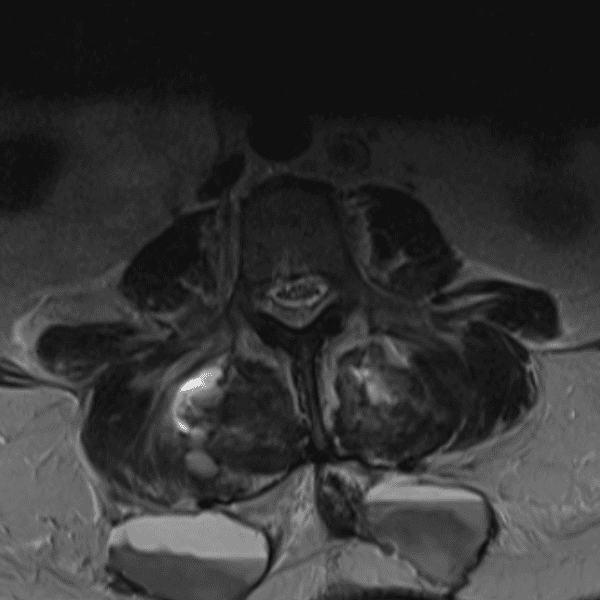

Simulates call by including subtle or difficult cases and some normals.

35 cases